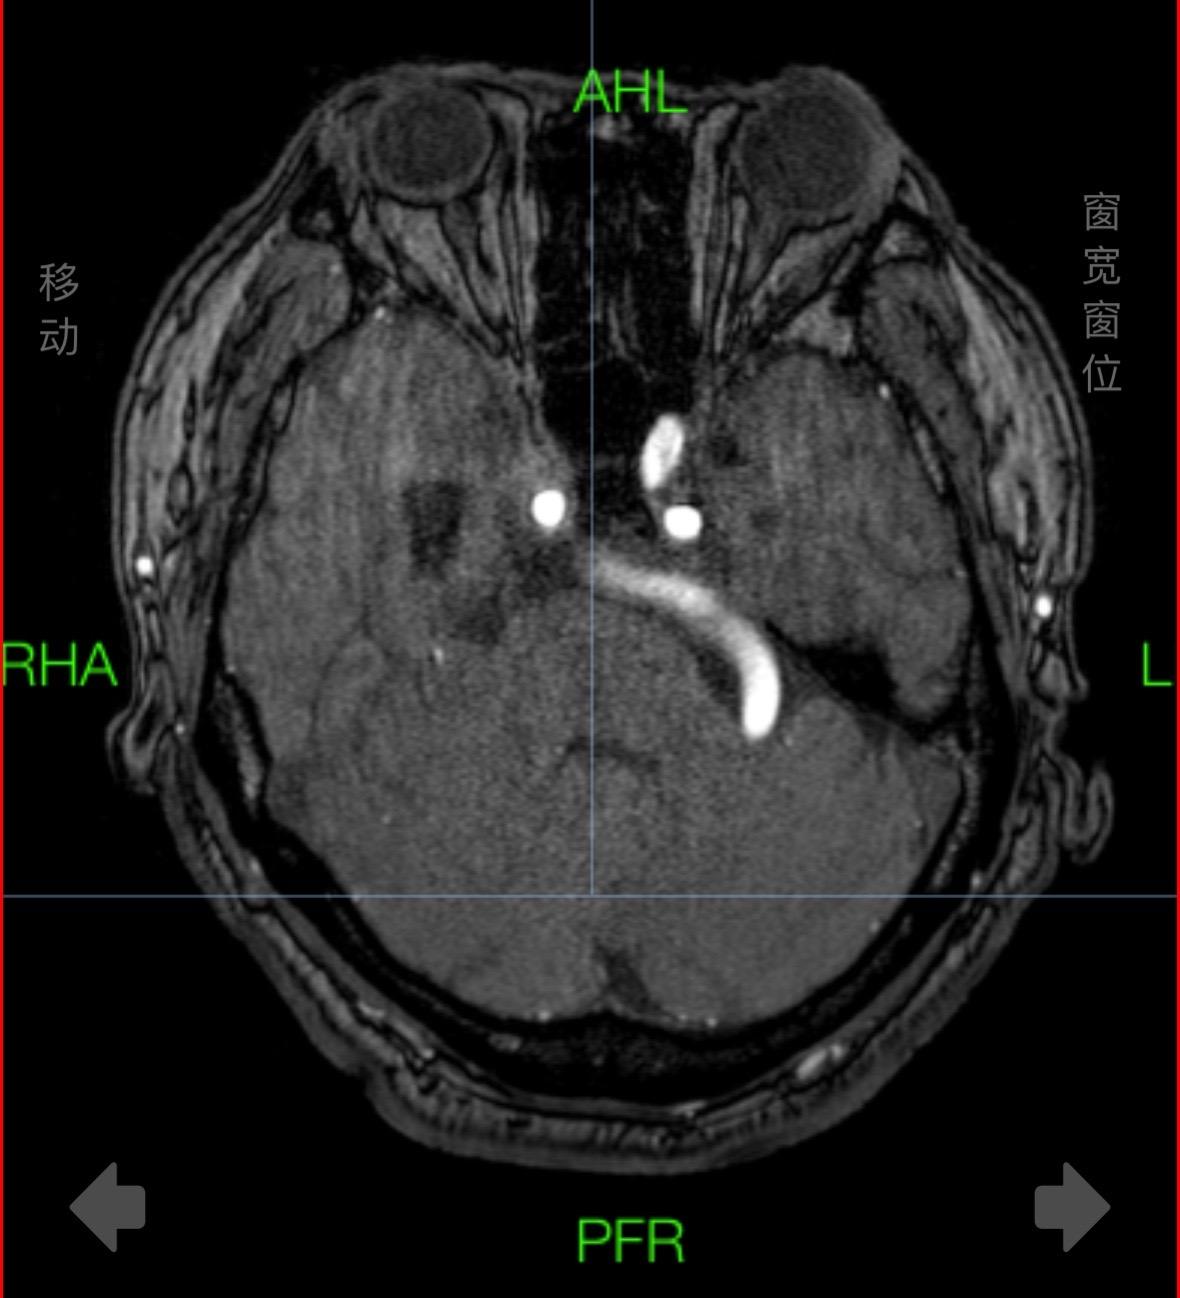

高温“烧死”肿瘤。利用机器人植入光纤,磁共振引导下高温消融颅内恶性肿瘤,看起来像科幻片,需要大量人力和高端设备加持!